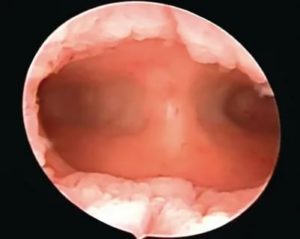

- Гистероскопия – полостное исследование матки. В основе лежит особое оборудование с качественной оптикой, за счёт чего эндометрий тщательно рассматривается. Во время процедуры проводится выскабливание или прицельная биопсия.